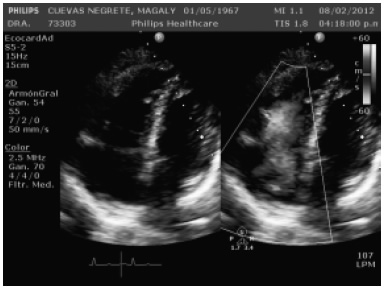

Persistió con actividad tumoral, por lo que se inició tratamiento con R-ICE (rituximab + ifosfamida + carbopaltino + etoposido) tres ciclos. En febrero 2012 se diagnosticó insuficiencia cardiaca secundaria probablemente a tratamiento quimioterapéutico. Con ECOTT dilatación de cavidades derechas (Figura 1), FEVI 45%, insuficiencia tricúspide moderada, TPSE 13 y PSAP de 78 mmHg. Se trató como falla cardiaca aguda y respondió a tratamiento en la Unidad Coronaria. No se pudo determinar la causa de la insuficiencia cardiaca, pero en los meses posteriores, la paciente presentó mejoría de la función ventricular izquierda, pero persistió con datos de falla cardiaca derecha.